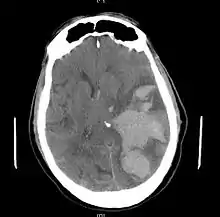

Treatment involves removal of the etiologic mass and decompressive craniectomy. Brain herniation can cause severe disability or death. In fact, when herniation is visible on a CT scan, the prognosis for a meaningful recovery of neurological function is poor.[2] The patient may become paralyzed on the same side as the lesion causing the pressure, or damage to parts of the brain caused by herniation may cause paralysis on the side opposite the lesion.[10] Damage to the midbrain, which contains the reticular activating network which regulates consciousness, will result in coma.[10] Damage to the cardio-respiratory centers in the medulla oblongata will cause respiratory arrest and (secondarily) cardiac arrest.[10] Investigation is underway regarding the use of neuroprotective agents during the prolonged post-traumatic period of brain hypersensitivity associated with the syndrome.[16]